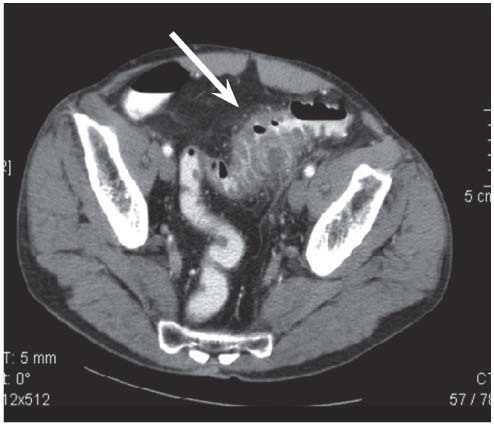

Patient hospitalisée pour douleurs en FIG, fièvre. qu’est ce que c’est?

Diverticulite aiguë sigmoïdienne